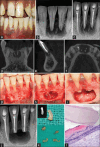

Periapical lesions with mixed radiographic appearance can have odontogenic or nonodontogenic origin. A number of neoplastic lesions either benign or malignant can present as radiolucent, radiopaque, or mixed in jaws and if present near the root apices can be misdiagnosed as odontogenic infection/etiology. The present case report describes a rare case of two elongated radiopaque structures within periapical pathology located beneath the apices of mandibular central incisors in a 26-year-old male. Further, it describes its nonsurgical and surgical endodontic management along with histological confirmation and long-term radiographic healing outcome using cone-beam computed tomography. Microscopic examination revealed the presence of dentin and cementum with fringes of periodontal ligament suggestive of tooth-like structures. No case report has yet reported tooth-like calcifications within the large periapical lesion. Biopsy of such lesions is deemed necessary to differentiate from nonodontogenic lesions which could be benign or malignant in nature.